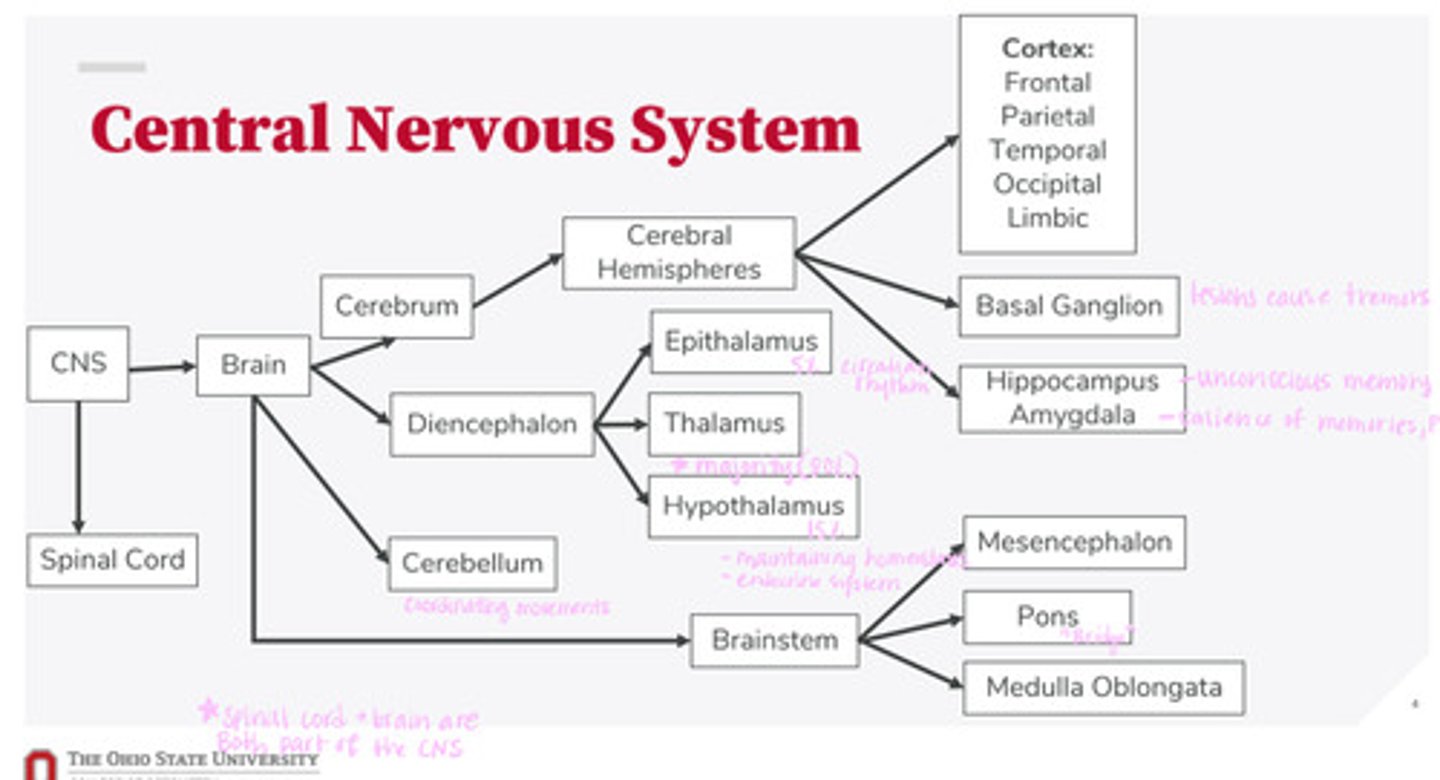

-brain

-spinal cord

What are the 2 divisions of the CNS?

-cerebrum

-diencephalon

-cerebellum

-brainstem

What are the 4 divisions of the brain?

-epithalamus

-thalamus

-hypothalamus

What are the 3 divisions of the diencephalon?

-mesencephalon

-pons

-medulla oblongata

What are the 3 divisions of the brainstem?

-cortex

-basal ganglion

-hippocampus

-amygdala

What are the divisions of the cerebral hemispheres?

-frontal lobe

-parietal lobe

-temporal lobe

-occipital lobe

-limbic system

What are the divisions of the cortex?

coordinating movements

What is the function of the cerebellum?

thalamus

A majority of signals from the diencephalon flow into where?

circadian rhythm

What is the function of the epithalamus?

-maintaining homeostasis

-endocrine system function

What is the function of the hypothalamus?

tremors

Lesions on the basal ganglion cause what?

hippocampus

What part of the brain is in control of unconscious memory?

amygdala

What part of the brain is in control of the salience of memories (PTSD)?

The bridge between the mesencephalon and the medulla oblongata

What is the function of the pons?